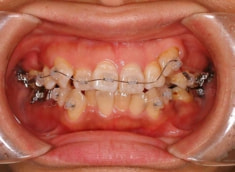

治療前

治療開始時